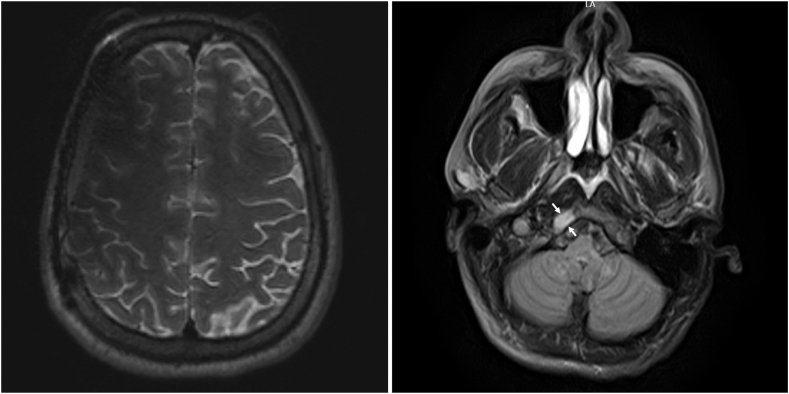

Our patient was a 31-year-old man diagnosed with periaortic PGL and succinate dehydrogenase subunit B pathogenic variant at the age of 9 years with cardiac arrest. He developed intra-abdominal and skeletal metastatic disease by the age of 14 years and treated with surgery, chemotherapy, and radiation. After being lost to follow-up, the patient presented emergently with headache, palpitations, hypertensive crisis, type 2 non-ST-elevation myocardial infarction, and catecholamine-induced cardiomyopathy, with plasma free metanephrine level of 61.0 pg/mL (0.0-88.0 pg/mL) and elevated serum free normetanephrine level of 662.9 pg/mL (0.0-210.1 pg/mL). Imaging showed a right frontal calvarial lesion, with 4.9-cm intracranial dural and 4.9-cm extracranial components, and a 1.5-cm occipital bone lesion. Following adrenergic blockade, the patient underwent resection of the frontal lesion with pathology showing metastatic PGL.